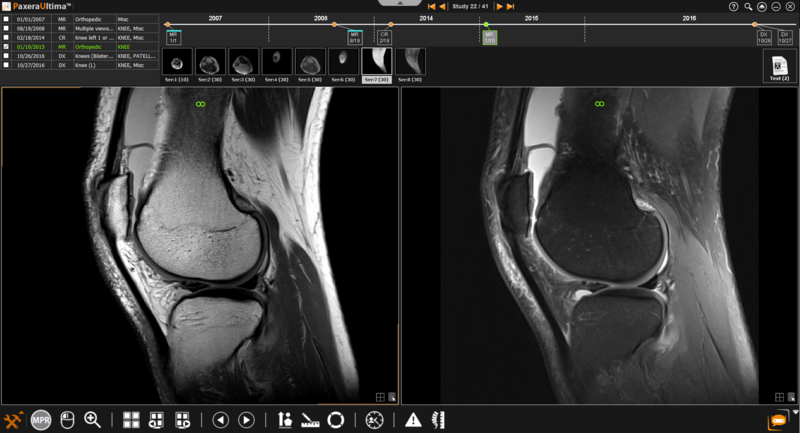

1.          Select the two series that you would like to link by holding down the 'Ctrl" key and clicking on the series. Selected series will be outlined with a white box.

An infinity sign will be shown on the top of each image window to indicate that both series are linked.